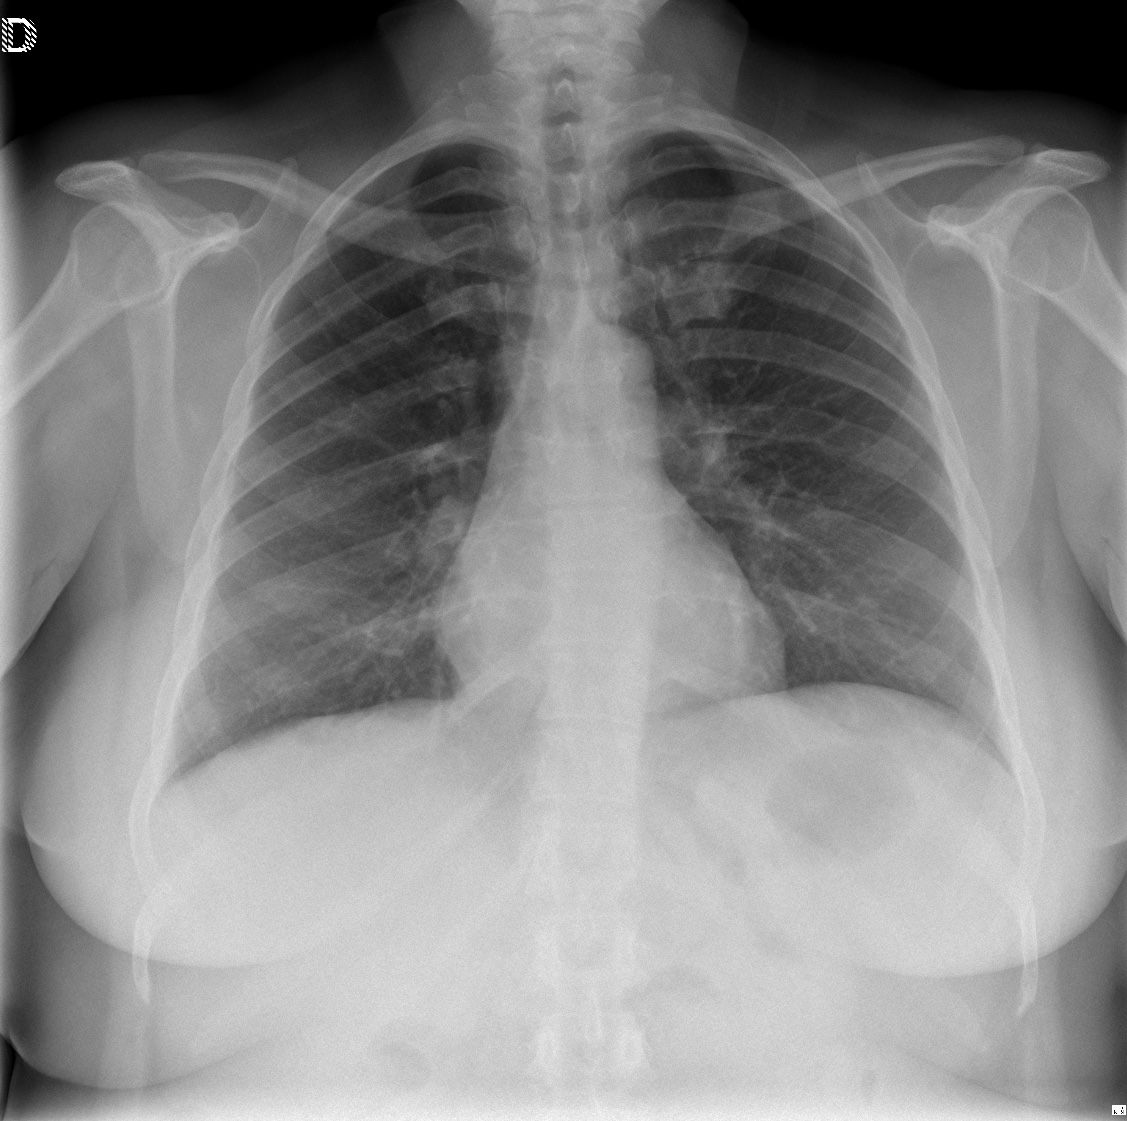

CASO: sospecha de neumonía.

Hallazgos:

- En un principio podríamos decir que existe un aumento de densidad retrocardiaco que podría ser compatible con condensación neumónica a dicho nivel, sin embargo estamos ante una placa poco inspirada, lo cual puede llevarnos a cometer errores diagnósticos.

- Se recomendó volver a realizar la radiografía, observar a continuación:

Ya no se observa el aumento de densidad retrocardiaco, la placa es normal.

INSPIRACIÓN: Una placa bien inspirada es aquella en la que se observar 6-7 arcos costales anteriores o 10-11 arcos costales posteriores. Lo contrario puede producir imágenes falsas de condensaciones o de seudocardiomegalia.